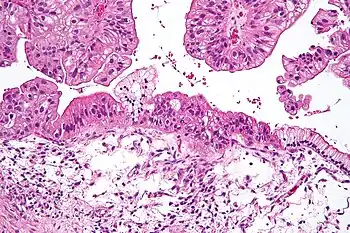

Benign mucinous tumors are typically multilocular (have several lobes), and the cysts have a smooth lining of epithelium that resembles endocervical epithelial cells with small numbers of gastrointestinal-type epithelial cells. Borderline and malignant mucinous tumors often have papillae and solid areas. There may also be hemorrhage and necrosis.

Cystadenocarcinomas (malignant tumors) contain a more solid growth pattern with the hallmarks of malignancy: cellular atypia and stratification, loss of the normal architecture of the tissue, and necrosis. The appearance can look similar to colonic cancer.

Clear stromal invasion is used to differentiate borderline tumors from malignant tumors.